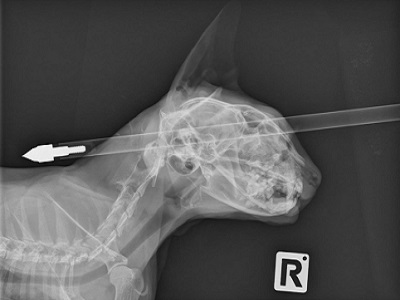

نجاة قط بعد إصابته بسهم في رأسه

نجا قط نيوزيلندي، بحياته بعد إصابته بسهم اخترق رأسه، حسب ما أعلن، اليوم، المستشفى الذي أجرى له عملية جراحية.

وأجرى الجراحون البيطريون، عملية جراحية لاستخراج السهم الذي كان بارزا من مقدمة ومؤخرة جمجمته.

وقال الجراح، جوناثان براي، إن "السهم اخترق الرأس من فوق العين مباشرة، ولم يؤثر على أنسجة المخ على الإطلاق"، مشيرا إلى أن العملية كانت بسيطة لأن السهم لم يصب المخ.

وقال براي، إن "هناك جرحا بسيطا في الأنف وتجويف العين، لكنه قط محظوظ للغاية".

وأضاف أن القط "في حالة جيدة للغاية صباح اليوم، متألق وسعيد، الجرح يلتئم بشكل جيد، وإصابته لن تضر به على المدى الطويل".